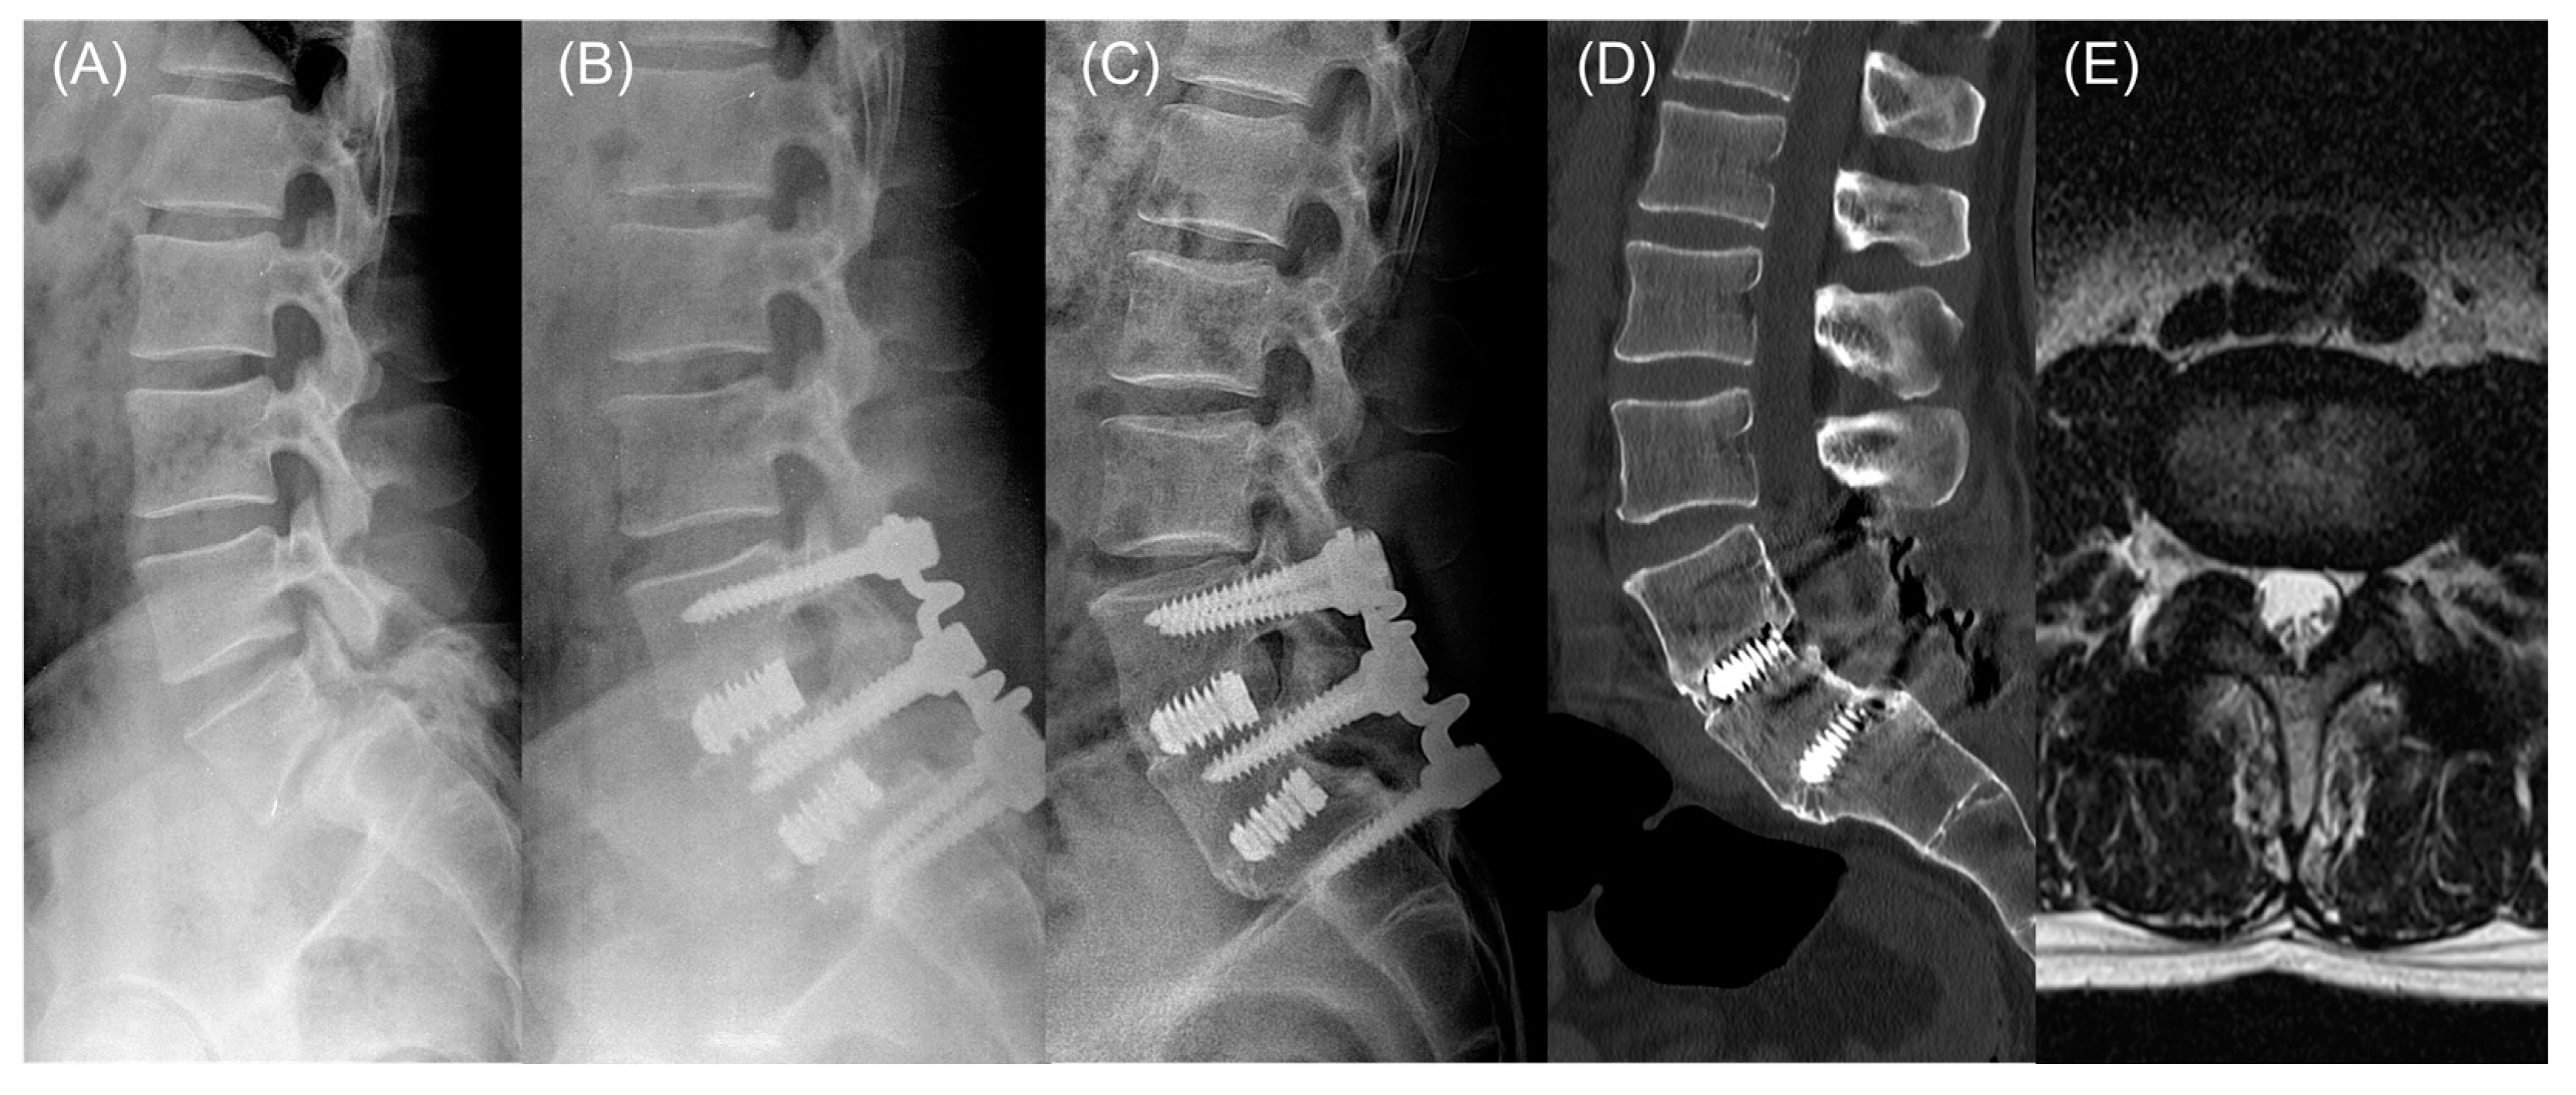

2.2. Surgical Procedure

2.3. Radiologic Outcome Measures

4. Discussion